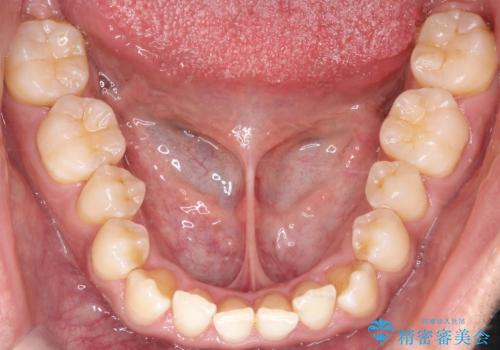

- 左上の八重歯を気にされて来院されました。精密な検査の結果、歯列全体を広げながら八重歯を奥へ移動させることで、美しい歯並びと機能的な咬み合わせが得られると診断。患者様のご希望に合わせ、透明で目立ちにくい**インビザライン(マウスピース矯正)**による治療計画を立案しました。抜歯を避け、歯を少しずつ遠心(奥)へ移動させることで、歯が並ぶスペースを確保し、叢生(歯のデコボコ)を改善します。

今回の矯正治療では、透明なマウスピース型の装置インビザラインを使用しました。この装置は目立ちにくく、取り外しが可能なため、食事や歯磨きも普段通りに行えます。遠心移動という方法で奥歯を後方に動かし、前歯を並べるためのスペースを確保。これにより、抜歯することなく、左上の八重歯を含む叢生を効果的に改善し、整った美しい歯並びと良好な咬み合わせを獲得していただけました。